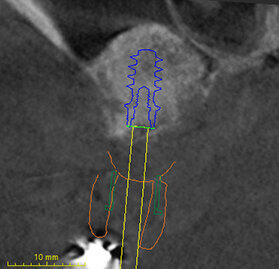

Nei casi di atrofie marcate, è fondamentale ricostruire l’osso mancante ma anche poter dare all’arcata una forma ideale. In questo caso clinico la paziente si presenta alla mia osservazione con una marcata atrofia del mascellare superiore (Fig. 1). La valutazione clinica è stata effettuata con esami radiografici di routine, OPM ed endorali, ma soprattutto con una Cone Beam TC. Da alcuni anni infatti, effettuo tutte le valutazioni diagnostiche in ambiente CAD con un software di chirurgia computer guidata che consente di valutare l’osso residuo in relazione al posizionamento tridimensionale dell’impianto protesicamente guidato.

L’approccio è quello di duplicare la protesi mobile utilizzata quotidianamente dalla paziente per renderla, attraverso punti di repere radiopachi, protesi radiologica. La paziente eseguirà la Cone Beam con la protesi radiologica e grazie alla presenza dei punti di repere radiopachi si potrà fare il matching tra i dati DICOM e la protesi della paziente (Figg. 2-4). Durante questa prima valutazione risulta evidente l’assenza di osso attorno agli impianti. La marcata perdita ossea è prevalentemente orizzontale e si estende in senso antero-posteriore su tutta l’arcata mascellare. Nella zona degli incisivi il posizionamento protesicamente guidato non è possibile a causa dell’assenza orizzontale dell’osso. Nelle zone posteriori inoltre si evidenziano i prolassi dei seni mascellari che riducono ulteriormente la disponibilità ossea. Di fronte a un quadro clinico così complesso si rende necessaria una scelta oculata della tecnica ricostruttiva adeguata.

Stabilita la tecnica rigenerativa è necessario fare delle valutazioni sul periodo post operatorio e quindi sul tipo di protesi provvisoria da far indossare alla paziente. Escludendo tutte le tipologie di protesi mobili per almeno sei mesi (compresa quindi una protesi sostenuta da un impianto posizionato nel palato), sempre con l’ausilio del software di chirurgia guidata ho quindi ipotizzato l’inserimento di due impianti nella zona della tuberosità (Fig. 5). Con l’ausilio della dima chirurgica sono stati inseriti tre impianti, due nelle tuberosità mascellari e uno nel palato (Fig. 6). Sui tre impianti è stato progettato insieme ai tecnici un dispositivo in metallo che potesse sostenere dei denti fissi non rimovibili (Fig. 7). Il risultato ottenuto è stato eccellente perché la paziente ha portato una protesi fissa fin dal giorno dell’intervento per tutto il periodo di guarigione, di circa nove mesi. La progettazione della ricostruzione ossea è stata quindi fatta in maniera Protesicamente Guidata, sono stati posizionati gli impianti virtuali e poi valutata l’entità della rigenerazione necessaria.

Inoltre da questa nuova ceratura dobbiamo ricavare una protesi radiografica con i punti di repere radiopachi che ci servirà per fare il matching con i nuovi file DICOM dell’osso rigenerato (Figg. 35, 36). Fatte le opportune verifiche nel software di chirurgia guidata, si pianifica l’intervento di posizionamento implantare (Figg. 37-40). Si programma lo stesso giorno della chirurgia anche il carico immediato degli impianti; decisione supportata dalla verifica istologica dell’osso rigenerato che dovrà comunque essere confermata il giorno del posizionamento implantare durante il quale si misurerà il torque di inserimento degli impianti e la stabilità primaria con il sistema OSSTELL mentor (Integration Diagnostics) che sfrutta l’analisi della frequenza di risonanza.

Grazie al flusso digitale, possiamo inserie nel software anche il file STL del provvisorio pre-chirurgico preparato e quindi progettare il provvisorio immediato (Fig. 41). La pianificazione degli impianti a questo punto viene effettuata in modo protesicamente guidato ed è facile posizionare correttamente l’impianto e verificarlo nelle cross del software. Si progetta e si disegna quindi la dima chirurgica (Fig. 42). Il giorno dell’intervento abbiamo già tutto pronto e la paziente presenta uno stato di salute dei tessuti ottimale grazie anche al fatto che ha potuto portare per tutto il periodo una protesi fissa.